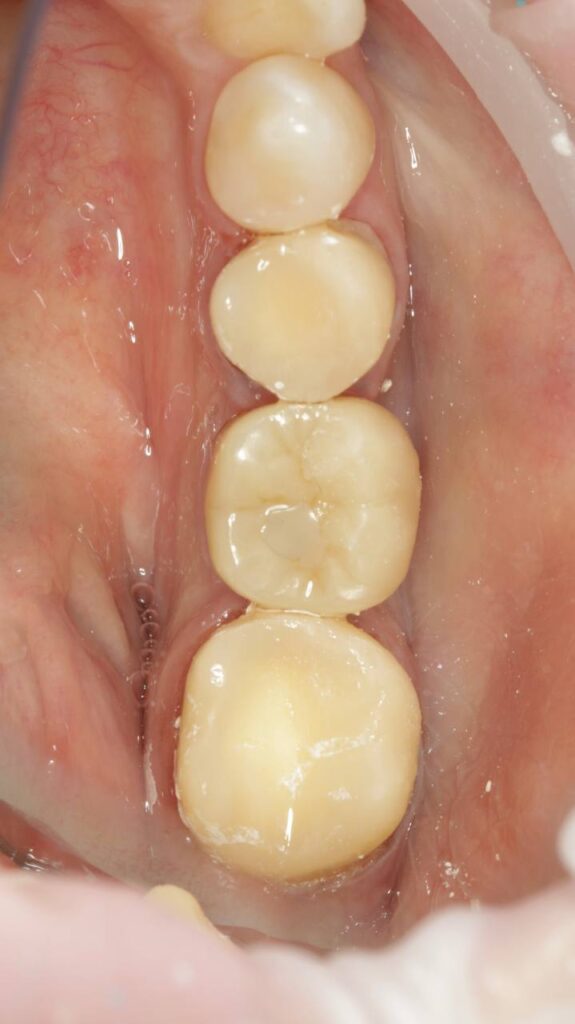

Протезирование коронками из диоксида циркония, после эндодонтического лечения — Исламов Л.А.(01.04.2026)